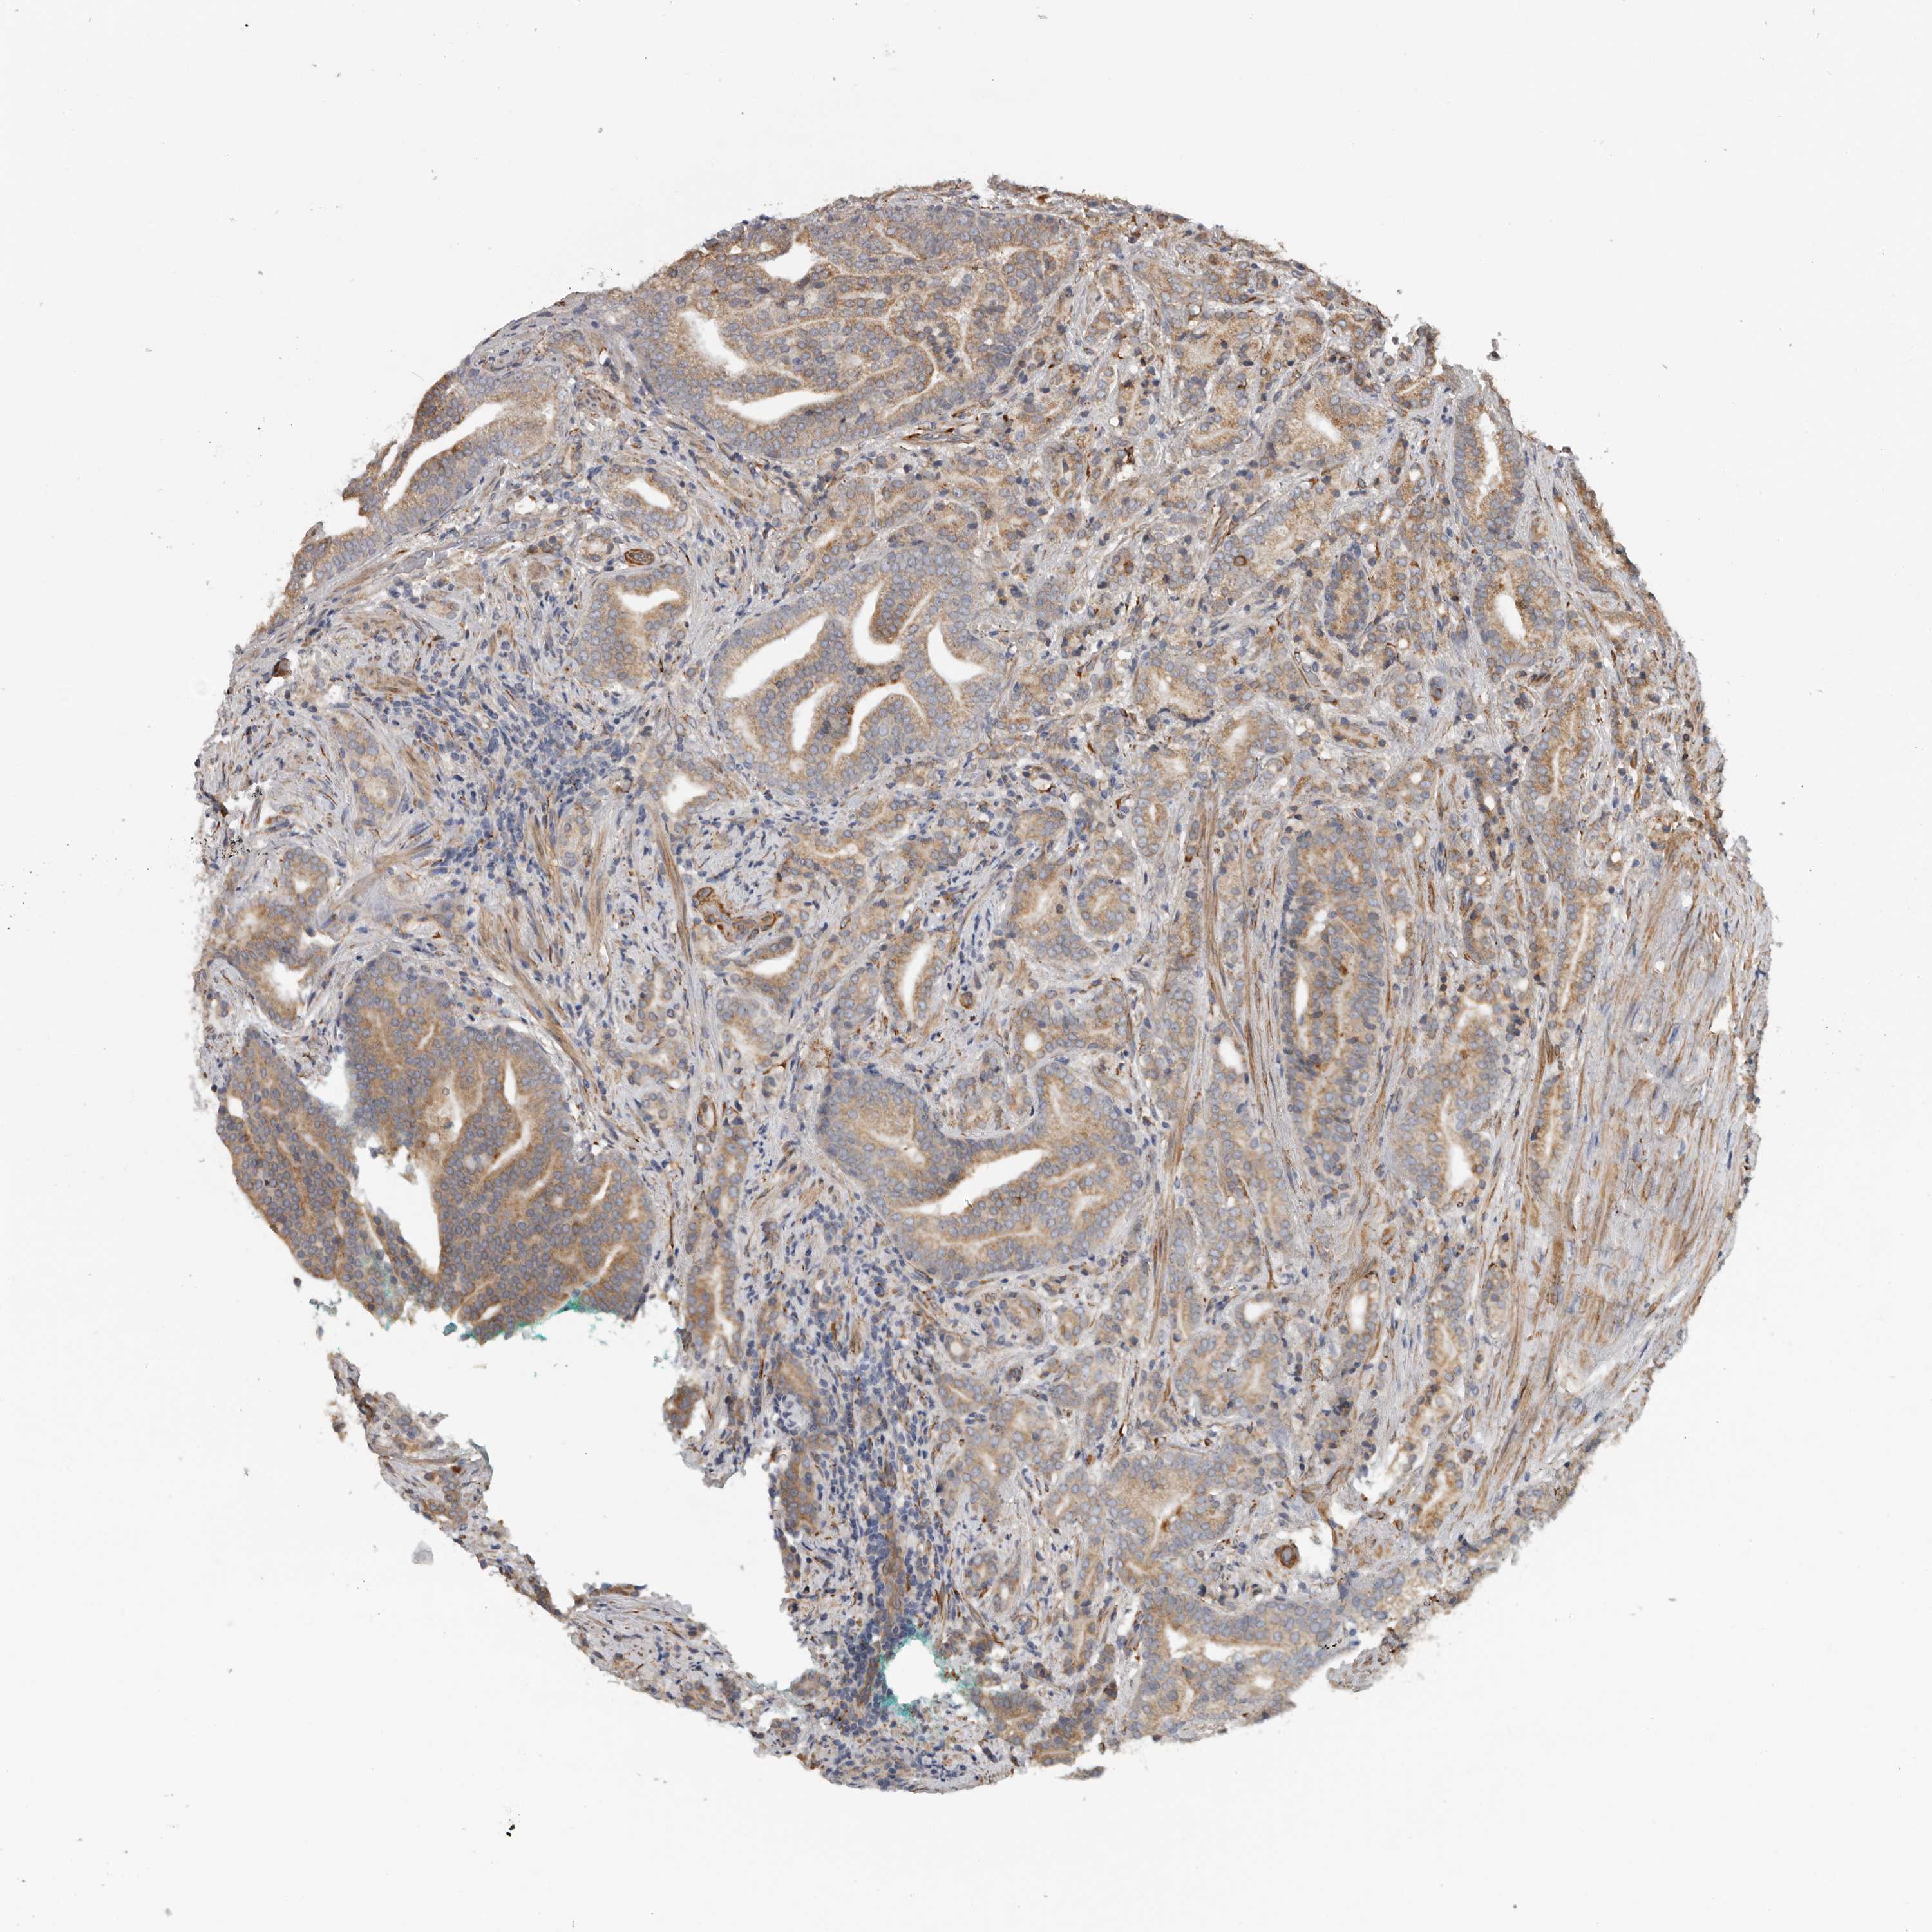

PROSTATE CANCER - Protein expressioni

A mouse-over function shows sample information and annotation data. Click on an image to view it in a full screen mode. Samples can be filtered based on level of antibody staining by selecting one or several of the following categories: high, medium, low and not detected. The assay and annotation is described here.

Note that samples used for immunohistochemistry by the Human Protein Atlas do not correspond to samples in the TCGA dataset.

Antibody stainingi

Antibody staining in the annotated cell types in the current human tissue is reported as not detected, low, medium, or high, based on conventional immunohistochemistry profiling in selected tissues. This score is based on the combination of the staining intensity and fraction of stained cells.

Each image is clickable and will lead to virtual microscopy that enables deeper exploration of all samples and also displays staining intensity scores, fraction scores and subcellular localization as well as patient and tissue information for each sample.

Antibody HPA028355

Antibody HPA028357

Staining

High

Medium

Low

Not detected

Intensity

Strong

Moderate

Weak

Negative

Quantity

>75%

75%-25%

<25%

None

Location

Nuclear

Cytoplasmic/membranous

Cytoplasmic/membranous,nuclear

Adenocarcinoma, High grade

Adenocarcinoma, Low grade

Adenocarcinoma, Medium grade